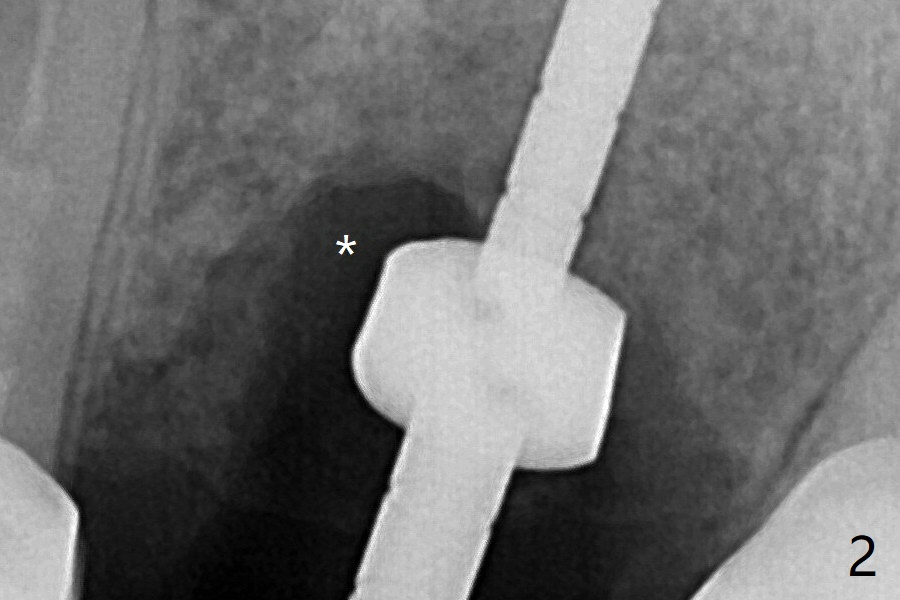

左上6腭侧退缩牙龈(图一:箭头)深部没有骨壁(图二:*),4.5x11毫米植体周围缺损(图三:*)由粘性骨粉(皮质骨,图四:*)填入。术后四个月骨粉形态接近原位骨(图八),但是腭侧软硬组织仍有缺损,炎症。